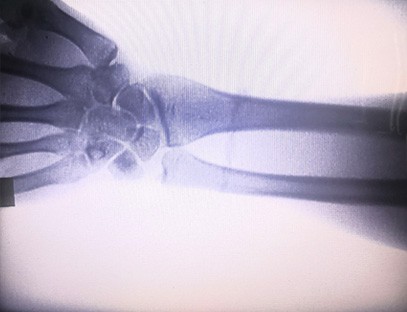

As-c200 bärbar röntgenmaskin är ett bärbart instrument med liten stråldos och mycket säker. Den är särskilt lämplig för enheter och individer med otillräcklig budget och låga krav på bilder. Den nya generationen är utrustad med en 10 tums högupplöst stor skärm, som har ett större perspektivområde och kan perspektivera hela handflatan fullt ut. Det är mest lämpligt för medicinskt ortopediskt perspektiv. Den kan kopplas till en filmskrivare för att skriva ut ortopediska filmer, och kan även användas i industriell produktion och testning. Inget mörkrum, direkt perspektiv, omedelbar observation, hög upplösning och tydlig bild.

Vår ortopedisk röntgenmaskin är en högkvalitativ produkt som designades speciellt för ortopedisk bildbehandling. Den kan användas för diagnos och behandlingsplanering av olika ortopediska tillstånd, inklusive frakturer, dislokationer, artrit och bentumörer. Den är utrustad med avancerad röntgenteknik som möjliggör högkvalitativa bilder med reducerad strålningsexponering. Maskinen har ett högupplöst bildsystem och kan ta bilder av vilken benstruktur som helst med stor tydlighet.

1. Avancerad bildteknik: Vår ortopediska röntgenmaskin använder avancerad bildteknik för att fånga högkvalitativa bilder av ben och leder, vilket ger korrekta diagnoser och förbättrade behandlingsresultat.